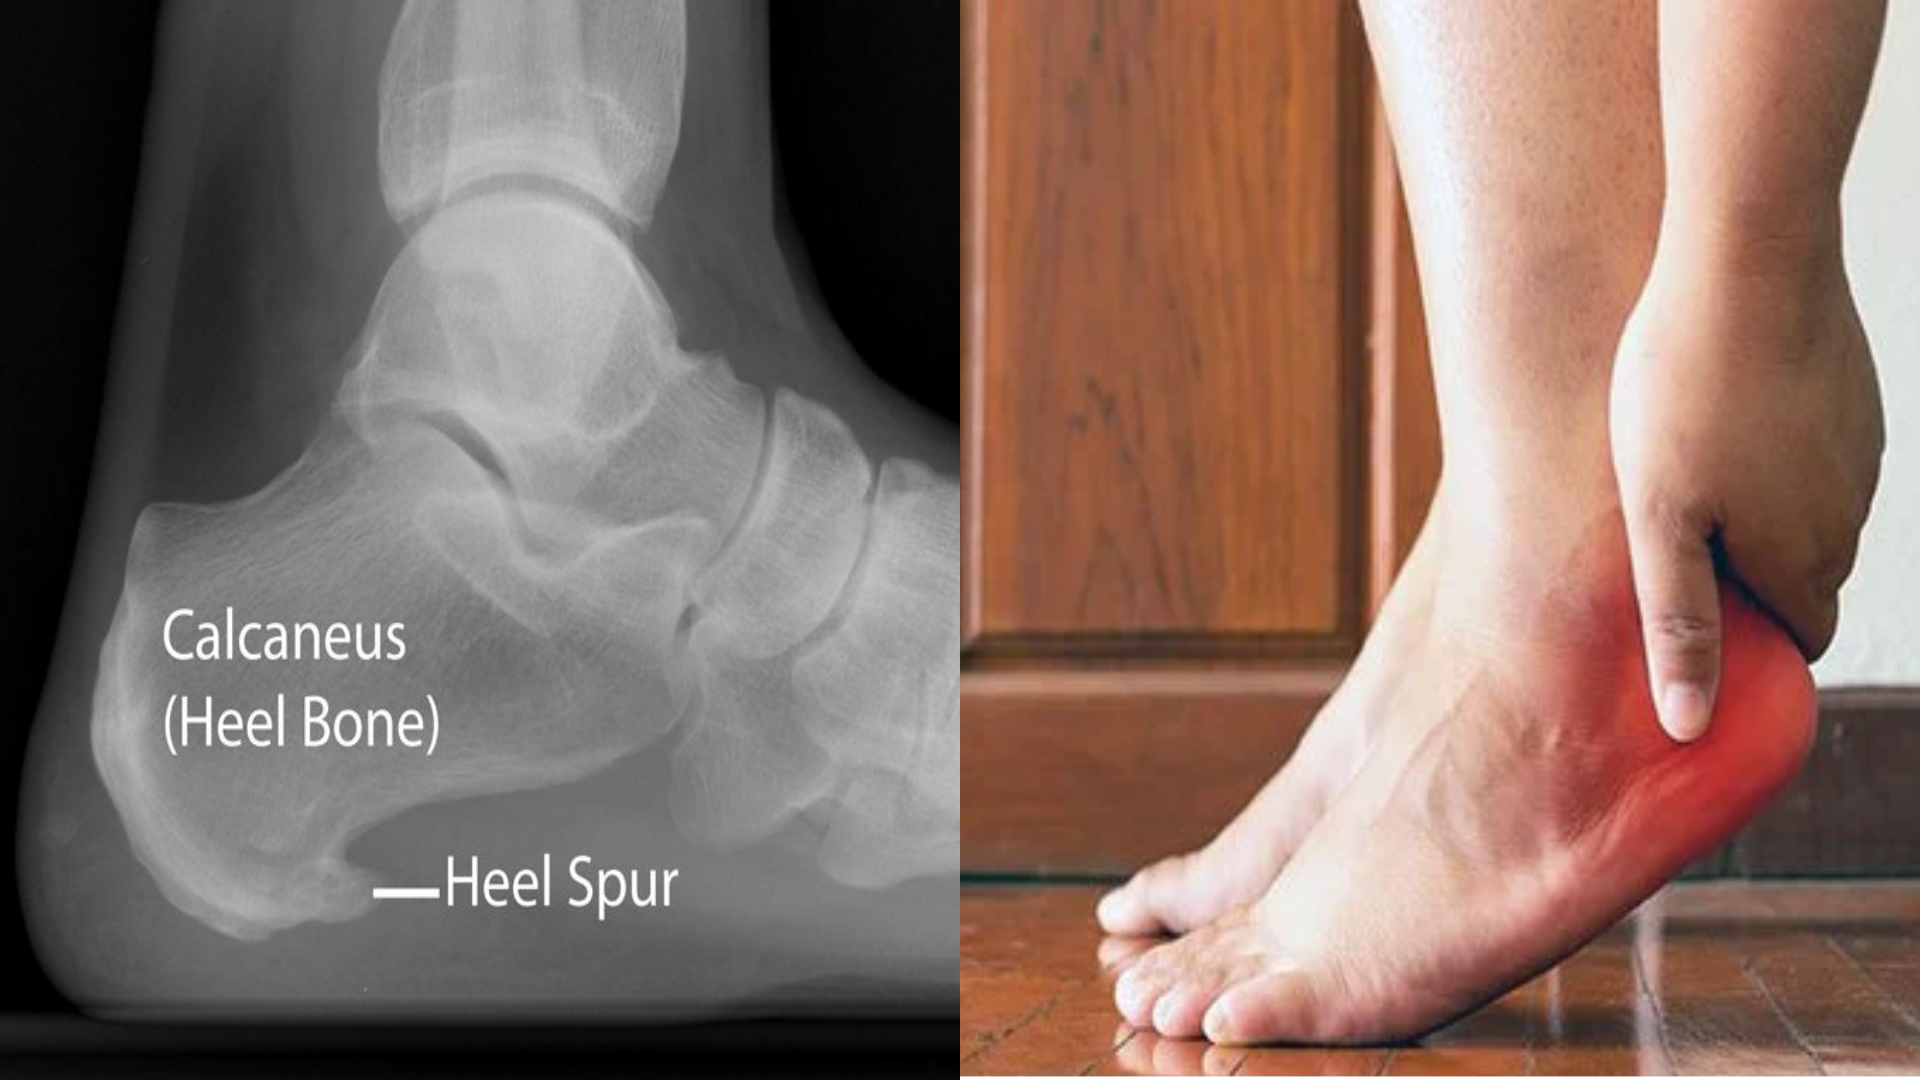

Calcaneal spur